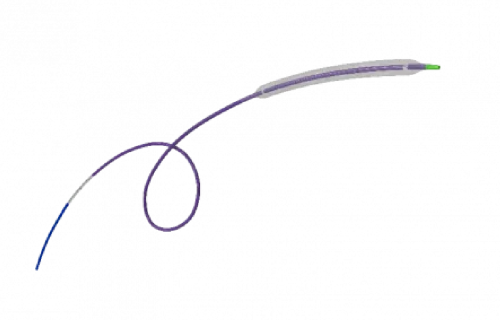

Na área de Cardiologia Intervencionista, fornecemos dispositivos de ponta, como stents, cateteres e balões, que são essenciais para a realização de angioplastias e outros procedimentos cardíacos minimamente invasivos. Nossos produtos são projetados para oferecer máxima eficiência e segurança, contribuindo para a rápida recuperação dos pacientes e a redução de complicações pós-operatórias.

Em Cirurgia Vascular, Endovascular e Radiologia Intervencionista oferecemos uma ampla gama de soluções, incluindo enxertos endovasculares, cateteres de trombectomia e dispositivos de embolização. Esses produtos são vitais para o tratamento de doenças vasculares complexas, como aneurismas e tromboses, proporcionando aos profissionais de saúde as ferramentas necessárias para intervenções precisas e eficazes.

Nossa atuação em Neurorradiologia Intervencionista inclui a oferta de microcateteres e stents especializados para o tratamento de aneurismas cerebrais e outras condições neurológicas críticas. Esses dispositivos são desenvolvidos com tecnologia de ponta para garantir a máxima segurança e eficácia durante os procedimentos, ajudando a preservar a integridade cerebral dos pacientes.